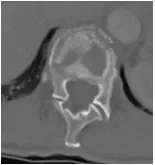

48 yo Female had a sledding injury when she landed on her buttocks following a fall. She felt a “pop” and immediate back pain. She was able to walk briefly, but quickly incapacitated by pain. Her examination suggested an injury to the lower thoracic spine. She was neurologically intact. She had uncontrolled pain. X Rays and CT scan of the patient showed fracture of T12 vertebral body.

The fracture was stabilized by Minimal Invasive spine surgery with percutaneous pedicle screws in T11, 12 and L1 and rod fixation.